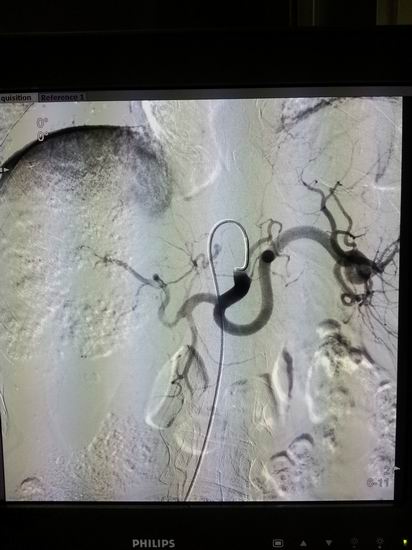

高档数字减影、血管造影系统 Allura Xper FD20

名称:高档数字减影、血管造影系统 Allura Xper FD20

主要功能:采用大平板科技,结合2K影像链,提供极佳图像细节解析能力,1250mA成像能力与“透心凉”高散热球管,“Refresh light”技术消除动态采集时的鬼影,图像质量更高。